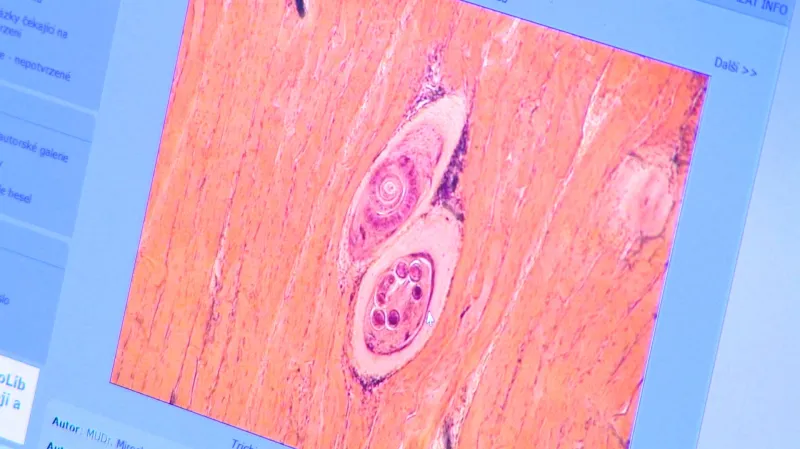

Parazit se přenáší krví. Vyskytuje se u prasat, ale také u psů, koček, medvědů, jezevců nebo lišek. Zvířata se nakazí masem zdechlin, člověk konzumací nedostatečně tepelně upraveného masa. Zpočátku se onemocnění projevuje bolestmi břicha a průjmem, v další fázi horečnatými stavy, bolestmi svalů, třesem, křečemi. Při velkém množství larev v těle může člověk zemřít.